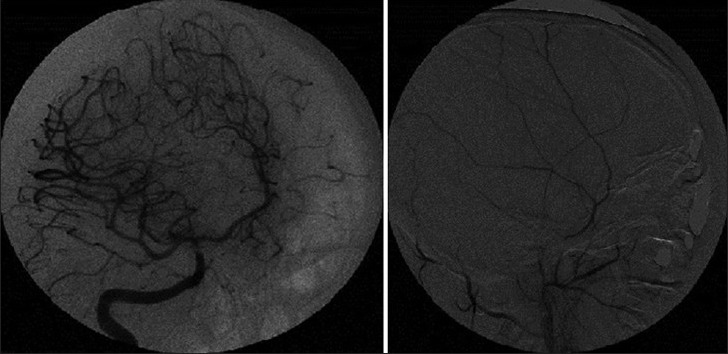

Figure 2.

DSA showing no evidence of any aneurysm or intra-cerebral or dural arteriovenous malformation

Figure 3.

The MCA branches are pushed medially by the extraaxial SDH on DSA